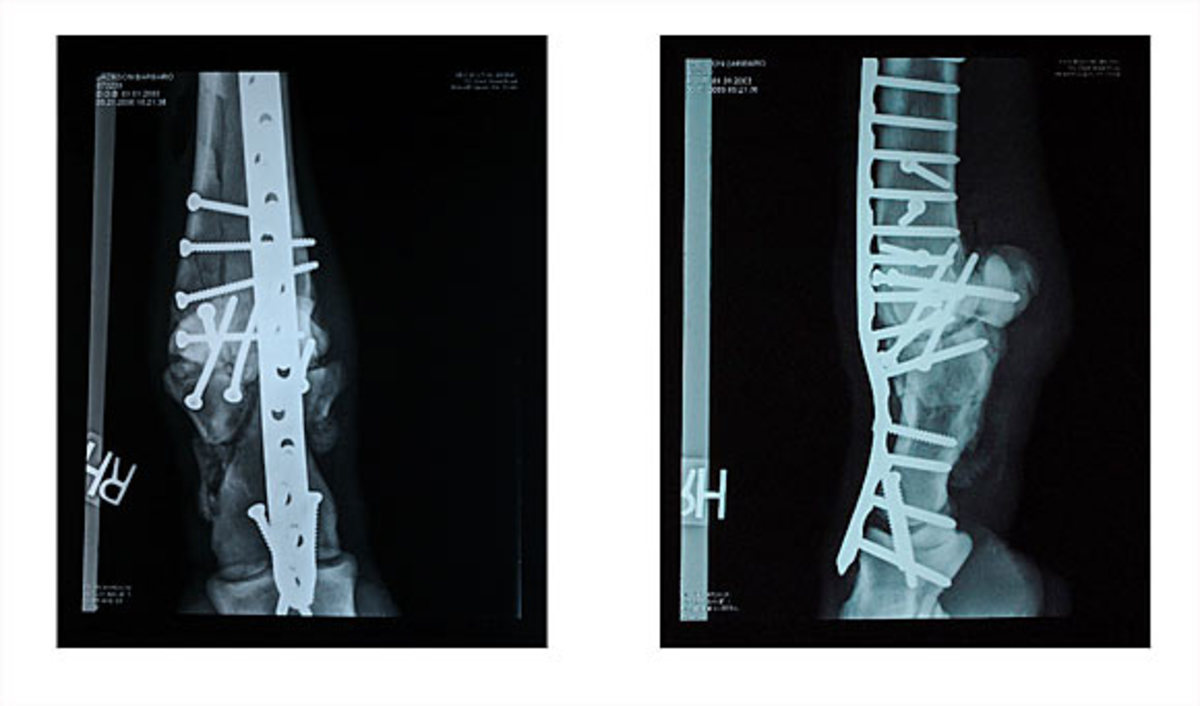

These X-rays, released by the University of Pennsylvania, show how Barbaro's right hind leg bone was held together using screws and plates. Unfortunately, while his right leg healed, Barbaro's left hind hoof would develop a severe case of laminitis.